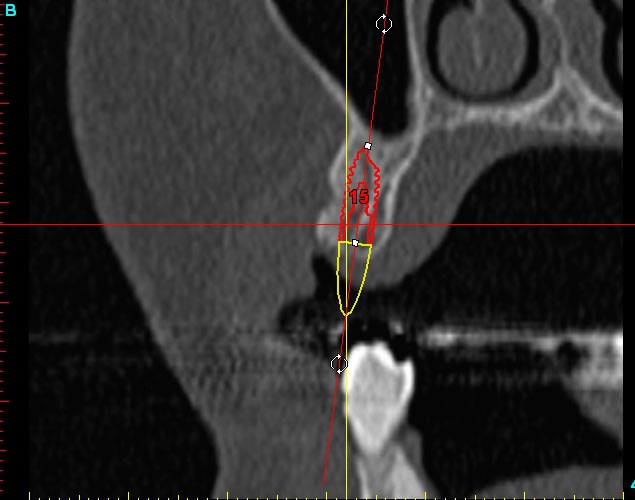

15dar srylok - Eugenol

Dar15 gpvqe1 - Eugenol

12